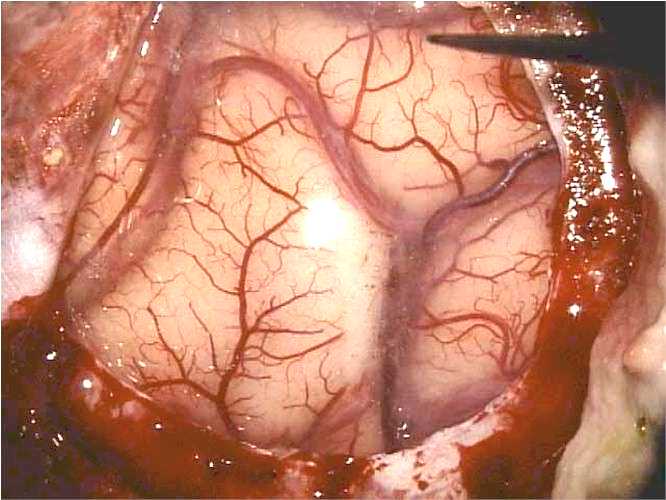

Attualmente, ciò che più garantisce al paziente di evitare deficit neurologici importanti è la possibilità di una chirurgia in anestesia locale, durante la quale il paziente è sveglio e collaborante. Questa modalità consente di eseguire un

mapping corticale intraoperatorio: l’area corticale a rischio viene stimolata elettricamente, mentre l’elettrocorticografia (EEG con elettrodi posti sulla superficie cerebrale) consente di determinare la corretta soglia di stimolazione.

Stimolazione

corticale a paziente sveglio |

Durante la stimolazione:

- Nel caso dell’area motoria, si osservano piccoli movimenti della mano o di altre parti del corpo.

- Nell’area somatosensoriale, il paziente segnala sensazioni lungo la metà controlaterale del viso o del braccio.

- Nell’area del linguaggio, il paziente esegue compiti verbali, come nominare oggetti mostrati durante la stimolazione o contare ad alta voce, permettendo di identificare con precisione le zone eloquenti.

Anche se queste informazioni possono sembrare minime, sono fondamentali per eseguire resezioni ottimali dei tumori senza provocare deficit neurologici permanenti.

Si tratta però di casi molto selezionati, che devono soddisfare specifici requisiti clinici e pratici. La maggior parte dei pazienti candidati sono giovani e affetti da lesioni di basso grado, nelle quali l’asportazione radicale garantisce una prognosi eccellente.